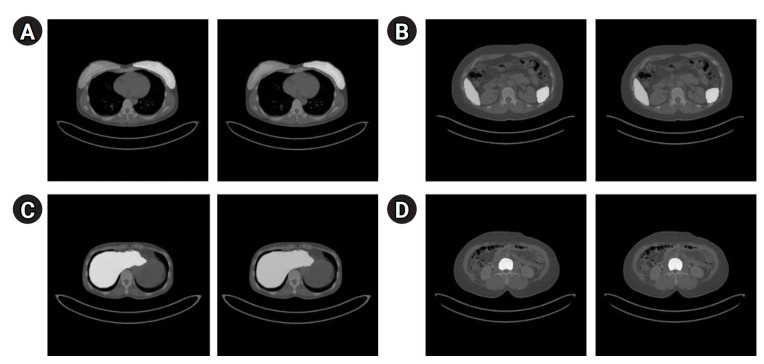

Methods: We used the Swin UNETR model to automatically segment key organs (breast, liver, spleen, and bone marrow) critical for breast cancer prognosis. Tumor segmentation was performed iteratively based on predefined SUV thresholds, and prognostic information was extracted from the liver, spleen, and bone marrow (reticuloendothelial system). The artificial intelligence training process employed 3 datasets: a test dataset (40 patients), a validation dataset (10 patients), and an independent test dataset (10 patients). To validate our approach, we compared the SUV values obtained using our method with those produced by commercial software.

Results: In a dataset of 10 patients, our method achieved an auto-segmentation accuracy of 0.9311 for all target organs. Comparison of maximum SUV and mean SUV values from our automated segmentation with those from traditional single-ROI methods revealed differences of 0.19 and 0.16, respectively, demonstrating improved reliability and accuracy in whole-organ SUV analysis.